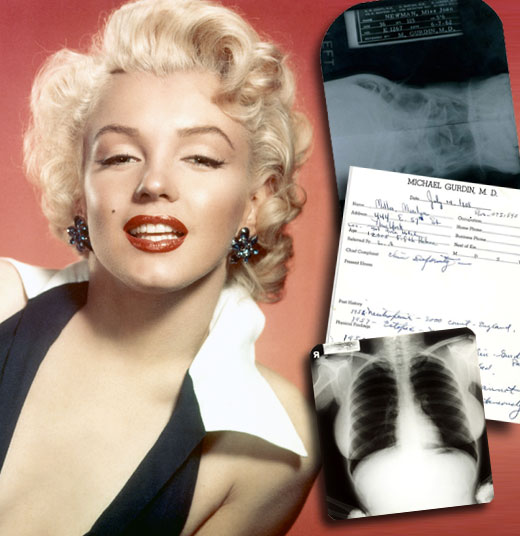

Marilyn Monroe: belleza... ¿natural?

El médico Michael Gurdin sacó a la luz pública reveladores informes médicos, que serán subastados en Beverly Hills, que demuestran que la actriz se sometió a un implante de cartílago en su barbilla en 1950 con el fin de potenciar su atractivo físico.

Las notas escritas por el Dr. Michael Gurdin comenzaron en 1958, cuando la actriz lo consultó por una "deformidad en el mentón". Aquí figura con su nombre de casada, Marilyn Miller, ya que había contraido matrimonio con el escritor Arthur Miller.

A las reveladoras notas escritas por el médico Michael Gurdin, supuestamente encargado de llevar a cabo la operación quirúrgica en 1950, se suman varias pruebas de rayos X realizadas el 7 de junio de 1962, dos meses antes del fallecimiento de la artista, en las que se pueden apreciar desde diferentes ángulos los huesos faciales de Marilyn, sus conductos nasales y su paladar.

"Nadie pensaba que Marilyn había acudido a un cirujano plástico. Hasta ahora eran meras especulaciones y siempre se había creído que poseía una belleza natural. Además, en esa época (años cincuenta) casi nadie se operaba, son técnicas que se consideran muy nuevas", comentó Martin Nolan, director de la casa de subastas Julien's Auctions, encargado de la venta de los citados informes médicos pertenecientes a la estrella del celuloide.

Radiografías de Marilyn Monroe, bajo el nombre de Marilyn DiMaggio, sacadas por un joven médico en 1954.

Se espera que estos reveladores documentos, entregados por el propio cirujano a un anónimo en forma de presente, lleguen a alcanzar entre los 15 y 30 mil dólares en la esperada subasta.